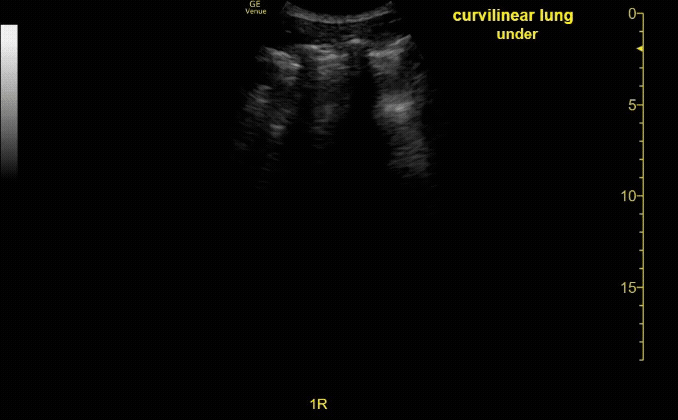

Thoracic ultrasound showing A-lines. Evaluate in 4 lung fields. Ensure a depth of 12-18cm.

c/o Victoria Gonzalez, MD